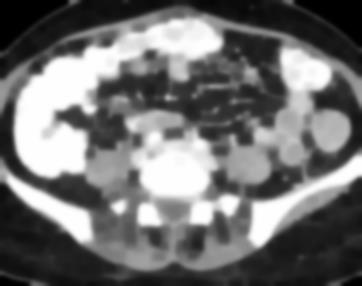

Due to the constraints of the imaging device and high cost in operation time, computer tomography (CT) scans are usually acquired with low intra-slice resolution. Improving the intra-slice resolution is beneficial to the disease diagnosis for both human experts and computer-aided systems. To this end, this paper builds a novel medical slice synthesis to increase the between-slice resolution. Considering that the ground-truth intermediate medical slices are always absent in clinical practice, we introduce the incremental cross-view mutual distillation strategy to accomplish this task in the self-supervised learning manner. Specifically, we model this problem from three different views: slice-wise interpolation from axial view and pixel-wise interpolation from coronal and sagittal views. Under this circumstance, the models learned from different views can distill valuable knowledge to guide the learning processes of each other. We can repeat this process to make the models synthesize intermediate slice data with increasing inter-slice resolution. To demonstrate the effectiveness of the proposed approach, we conduct comprehensive experiments on a large-scale CT dataset. Quantitative and qualitative comparison results show that our method outperforms state-of-the-art algorithms by clear margins.